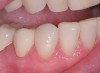

Figure 12  Case three retracted view. Note the rotation of the canine and lingual inclination of the premolars. Posterior disclusion in a lateral movement is not possible.

Figure 12

Patients often become concerned about the long-term viably of their teeth due to failing restorations. This patient was unhappy with the esthetics of her smile due to failing restorations and color. Unfortunately the patient’s anterior guidance was less than ideal due to her current tooth position. The axial inclination of her premolars was biased to the lingual. This tipping of the buccal cusps meant that in an excursive movement, the posterior teeth could not disclude. In addition, the canine teeth were rotated, leaving a deficit of needed contour (Figure 12).